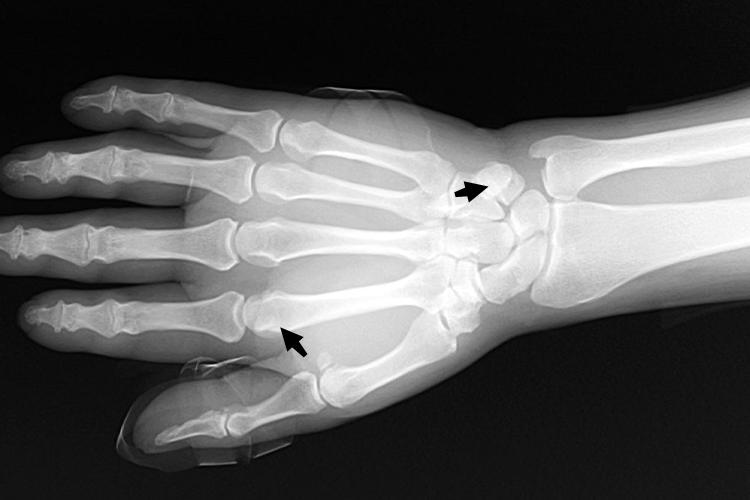

手籽骨是发生在某些肌腱内的扁圆形小骨,位于手部关节附近,与肌腱相连,共同构成关节的延伸部分,一般常出现在第2和第3块掌骨上。

在运动中,籽骨可减少肌腱与骨面的摩擦并改变骨骼肌的牵引方向,避免在运动和重体力的劳动过程中出现肌腱的磨损。